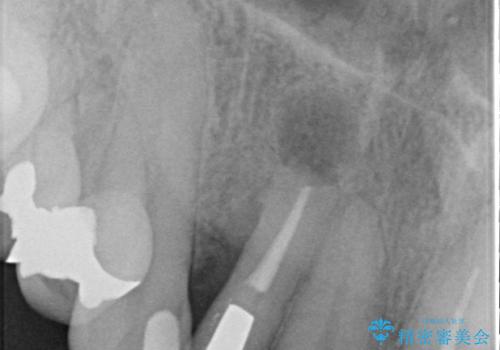

- 他院で治療したところ、右上2番目の歯の歯茎が下がってしまったので診て欲しいといらっしゃった方の症例です。

診査の結果右上2は歯根が破折しており、それが原因で骨及び歯肉の吸収が起きていました。

このまま右上2の抜歯を行うとさらに歯茎が下がる恐れがあったため、歯の挺出によって骨レベルを回復した上で抜歯し、歯槽堤保存術(抜歯窩に人工骨を填入する手術)を行いました。